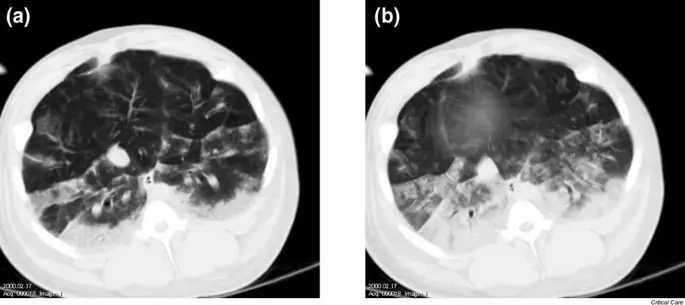

Спонтанное дыхание с использованием APRV / BiPAP при экспериментально вызванном повреждении легких было связано с меньшим образованием ателектаза в конечной экспираторной спиральной КТ целых легких и при сканировании над диафрагмой (рис. 1) (21). Хотя другие дыхательные мышцы могут также способствовать улучшению аэрации во время спонтанного дыхания, краниокаудальный градиент в аэрации, различия в аэрации и заметные различия в аэрации в областях, близких к диафрагме между APRV / BiPAP с спонтанным дыханием и без него, предполагают, что главную роль играют по диафрагмальным сокращениям наблюдаются различия аэрации (21). Эти экспериментальные данные подтверждаются наблюдениями с использованием электроимпедансной томографии для оценки регионарной вентиляции у пациентов с ОРДС, которые продемонстрировали лучшую вентиляцию в зависимых областях во время спонтанного дыхания с APRV / BiPAP (рис. 2). Экспериментальные данные свидетельствуют о том, что рекрутирование зависимых областей легких может быть вызвано в основном увеличением транспульмонального давления из-за снижения плеврального давления при спонтанном дыхании во время APRV / BiPAP (22).

Компьютерная томография области легкого над диафрагмой у свиньи с олеиновой кислотой, вызванной повреждением легкого при вентиляции с сбросом давления в дыхательных путях / двухфазным положительным давлением в дыхательных путях (а) с и (b) без спонтанного дыхания при сохранении равных пределов давления в дыхательных путях.